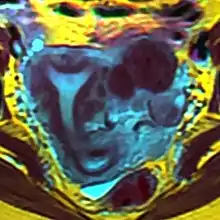

| Arcuate uterus (marked in red) seen on MRI | |